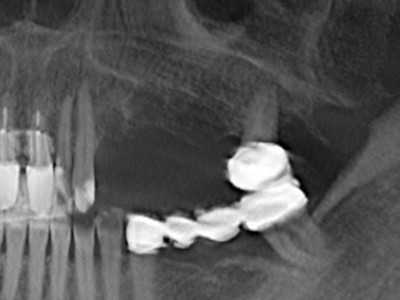

Indikation: Eigenknochengewinnung

Autologous bone transplants are used in the form of blocks, shells, rings and are also combined with bone replacement materials as chips. If the implant site is prepared at the same time as the augmentation, various bone filter systems have proven effective for collecting the resulting bone chips. As an alternative, the implant site can be prepared using a low-speed device without irrigation. If an implant is not inserted, bone chips can be harvested from the periphery with bone scrapers. This is also possible with piezo surgery using specialized attachments that yield higher-quality bone chips compared chips harvested with round drills, as has been confirmed in a study comparing the two methods (Chiriac, Herten et al. 2005).

Piezo surgery has additional advantages when harvesting bone blocks. In addition to the high precision with osteotomy described above, the use of the thin saw tips specifically minimizes loss of material. Greater loss of material during harvesting can be expected with the thicker instrument tips, particularly when using Lindemann drills (Lakshmiganthan, Gokulanathan et al. 2012). The basal separation, which is necessary particularly for retromolar block transplants, is simplified by specially designed rectangular saws, with the result that piezo surgery is viewed as a precise, simple and safe procedure for harvesting retromolar bone blocks (Happe 2007) (Fig. 1-12).